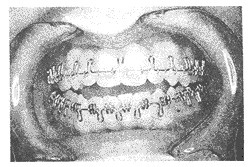

4.3 弓丝夹板 用0.53 mm×0.64 mm TMA或不锈钢丝(0.55 mm托槽)进行弯制(图7)。上下弓丝夹板弯制好后要求可顺利的进入托槽槽沟(passive),不给牙以任何力量。在用直丝托槽的患者,只需注意在水平和上下方向能就位,而对用标准方丝弓托槽者需在上牙弓前段作牙冠长轴一致的根舌向转矩,后段作牙冠舌向转矩;下牙弓前段与后段都作与牙冠长轴一致的冠舌向转矩。弓丝就位后用0.25 mm的结扎丝结扎。如为分段手术,术前可弯制前段牙弓的弓丝,手术中再弯制后牙部分,手术骨对位好后结扎固定。

图7 弓丝夹板